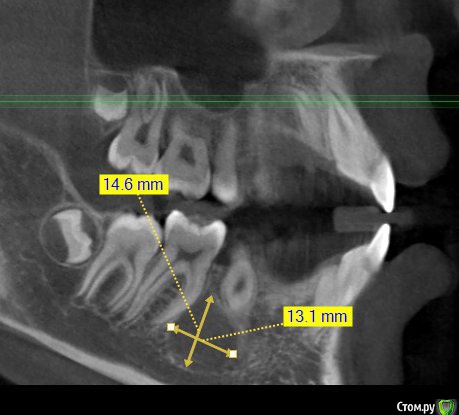

Kovalov Igor Опубликовано 14 июля, 2015 Поделиться Опубликовано 14 июля, 2015 (изменено) Уважаемые коллеги приветствую Вас! Встал вопрос стоит ли трогать фолликулярную кисту или наблюдать?Пациентка моя сестра, фолликулярная киста была случайной находкой, обнаружил ортодонт, отправил в областную больницу г. БелгородаВ детской ЧЛХ отказались, отправили в Харьков, это был 2013 год ещё. Во взрослой ЧЛХ не взялись, по возрасту. В детской члх сделали КТ, снимки и панораму прилагаю.Ps: картина за 2 года стала получше, но КТ сделают позже, есть внеротовой Rg снимок. Дело в том что я живу от сестры более 3000 км., сам бы это дело вскрыл амбулаторно, цистэктомия, графт+мембрана если гноя не будет... либо под йодоформом. Но вопрос стоит ли? и как по протоколу, каков Ваш план лечения? Депульпировать ли зубы 45-46? Изменено 14 июля, 2015 пользователем Kovalov Igor Ссылка на комментарий

Kovalov Igor Опубликовано 14 июля, 2015 Автор Поделиться Опубликовано 14 июля, 2015 вот Rg свежий. Вроде граница фолликулярной кисты уменьшилась.Как сделают КТ поделюсь тут... Буду признателен за ответы! Ссылка на комментарий